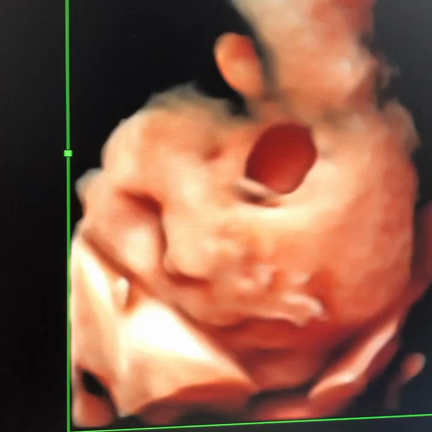

大阪府箕面市で分娩可能な助産院を2020年8月23日に開業致しました。分娩予約は随時受付中です♪自然なお産(赤ちゃんとママの力を最大限に活かして)のお手伝いをしたいと思い、妊娠中から産後までの助産師との関わりで素敵なマタニティライフと育児を楽しく過ごせると感じております。助産師として20年目になります。今まで総合病院やクリニックでの勤務経験だけでなく、地域の赤ちゃん訪問や小児の訪問看護など、ママと赤ちゃんをフォローすべく研鑽をして参りました。お一人お一人に必要なケアを提供して参りたいと思います。